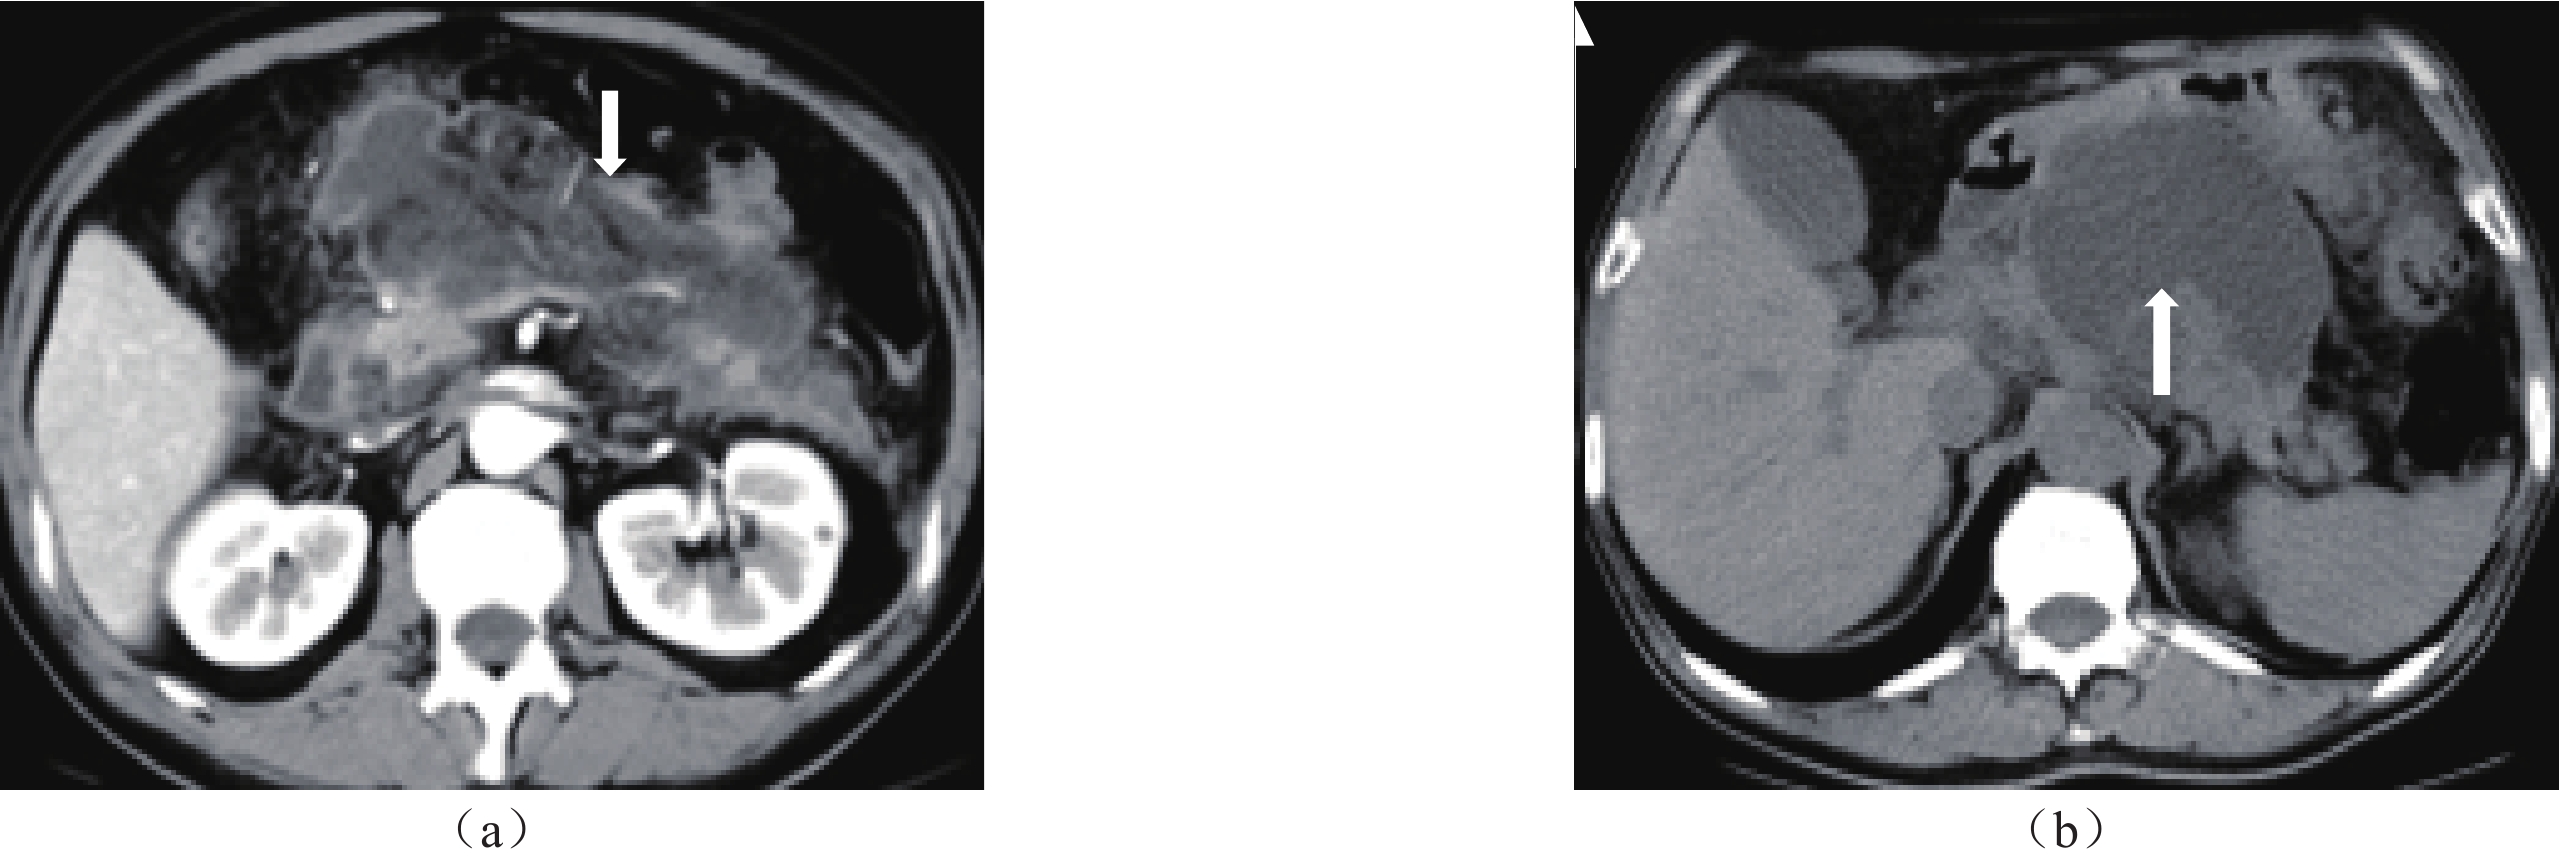

• 摘要: 目的:探究急性坏死性积聚(ANC)转归为包裹性坏死(WON)的独立危险因素及预测效能。方法:回顾性分析53例ANC的CT/MRI特征,根据ANC形成4周后的转归分为WON组与吸收组,采用卡方检验或t检验比较两组在病因、实验室检查方面差异的统计学意义。采用回归法分析影响ANC转归的独立危险因素,并绘制受试者操作特征(ROC)曲线,获得曲线下面积(AUC),评价各危险因素对ANC转归为WON的预测效能。结果:Logistic回归分析显示,坏死体积≥30%与MCTSI>6分的P值均<0.05,OR值分别为9.21和16.04。ROC曲线分析显示,坏死体积≥30%与MCTSI>6分的P值均<0.05,AUC值分别为0.86、0.88。结论:坏死体积≥30%与MCTSI>6分为ANC演变为WON的独立危险因素,且二者预测效能均较显著。

Abstract: Objective: To explore the independent risk factors and predictive efficacy of acute necrotic collection (ANC) conversion to encapsulated necrosis walled-off necrosis (WON). Methods: A Retrospective analysis of CT/MRI features in 53 cases of ANC, divided into the WON and absorption groups, based on the outcome after 4 weeks of ANC formation. The chi square test or T-test were used to compare the statistical significance of differences in etiology and laboratory tests between the two groups. Regression analysis was used to identify independent risk factors affecting the outcome of ANC. Receiver operating characteristic (ROC) curves were used to obtain the area under the curve (AUC) and evaluate the predictive efficacy of each risk factor for the outcome of ANC to WON. Results: Logistic regression analysis showed that the P-values for necrotic volume ≥ 30% and MCTSI score > 6 were both < 0.05, with OR values of 9.21 and 16.04, respectively. ROC curve analysis showed that the P-values for necrotic volume ≥ 30% and MCTSI score > 6 were both < 0.05, with AUC values of 0.86 and 0.88, respectively. Conclusion: Necrosis volume ≥ 30% and MCTSI score > 6 points are independent risk factors for the progression of ANC into WON, and the predictive performance of both is significant.